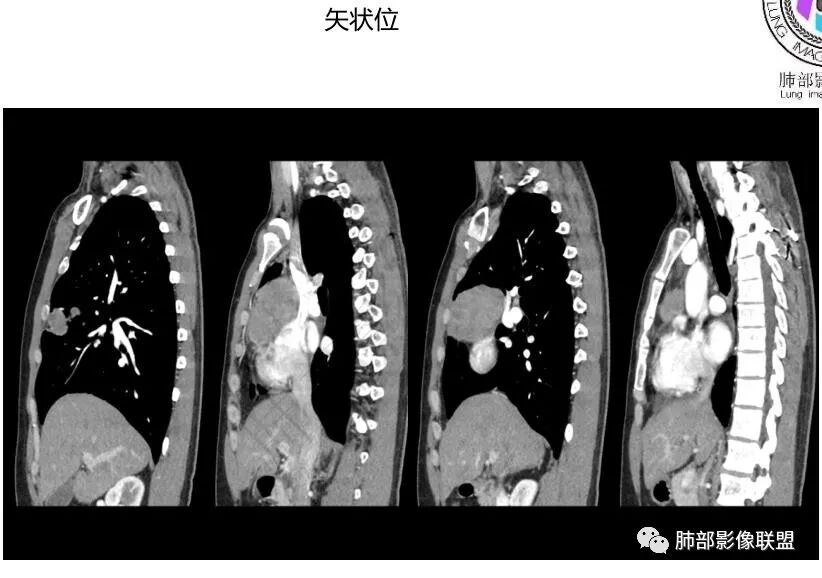

中青年男性,前纵膈偏右侧软组织肿块,形态不规则,有分叶,密度均匀,增强病灶轻中度强化,内部可见低或无强化区域,病灶与血管周围间隙分界不清晰,考虑恶性或交界性肿瘤,胸腺类癌>生殖细胞瘤>淋巴瘤。

前纵隔右侧见大肿块,边缘清,同侧内乳动脉增粗,渐进性延迟强化明显,强化密度不均匀,中心见偏低密度灶,上腔静脉内后侧推压移位(提示肿块质地偏硬),副神经节瘤,与巨淋巴细胞增生症鉴别。

青年男性,咳嗽,右上前纵隔不规则肿块,分叶,上腔静脉受压,内乳动脉增粗,延迟强化明显,坏死不明显,考虑来源纵隔,胸腺瘤,淋巴瘤,神经源性肿瘤都可以,比较年轻,猜个淋巴瘤吧。神经源性肿瘤代排。

前纵隔肿块,轻度分叶,边界不清楚,延迟强化,可见分隔,倾向恶性或具有一定侵袭性病灶。